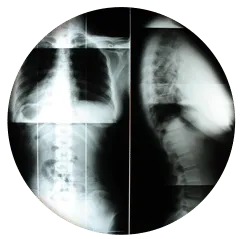

By aligning the spine and correcting issues with posture, balance, and correcting their proprioception, which affects issues within the inner ear and affects our spatial awareness, chiropractors can help reduce joint pain and soreness in the surrounding muscle and tissue.

Health care professionals who practice chiropractic care focus on the neuromusculoskeletal system of the body, and work to help patients eliminate pain, treat and prevent injuries and disorders of the muscles, bones, and nerves.

The primary objective of alleviating these issues is that by correcting nerve interference, by means of adjusting the spine, the body is able to heal itself without invasive procedures and drugs.

There are marshmallow like pads between your vertebrae called intervertebral discs. The discs are

very tough, but can be damaged. The discs provide for movement in the spine. When discs

start to degenerate the spine can become less mobile, and may even start to fuse together.

The discs also provide space between the vertebrae. This is important because nerves pass through the

spaces that are created by the discs. Discs also act as a shock absorbers. When movement occurs,

the jelly solution inside the disc has the ability to expand and compress. If the spine become misaligned,

a disc can become buldged or herniated. In some cases it may even rupture. A misalignment

is not the only cause for this problem. Age can cause the disc to become weak and dehydrated.